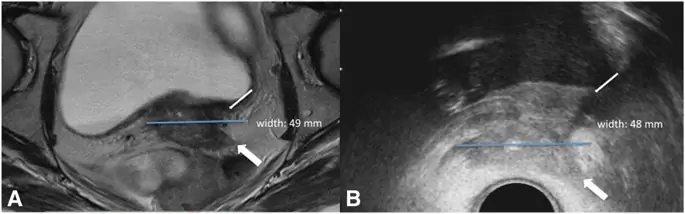

MRC HRCTV был определен как макроскопическое расширение остаточной опухоли, визуализированное на взвешенной МР T2, как масса высокой интенсивности сигнала, плюс потенциальные окружающие параметрические «серые зоны» с промежуточной интенсивностью сигнала в области начальной инфильтрации опухоли и оставшейся низкой интенсивностью сигнала стромы шейки матки (10). Пример приведен на рис. 1.

Случай рака шейки матки FIGO стадии IVA из-за инфильтрации мочевого пузыря. При МРТ (а) ширина опухоли составляет 49 мм. В preBT TRUS (б) ширина опухоли составляет 48 мм. Тонкие стрелки показывают вторжение задней стенки мочевого пузыря. Толстые стрелки показывают параметрическое вторжение

Изображение в полном размере